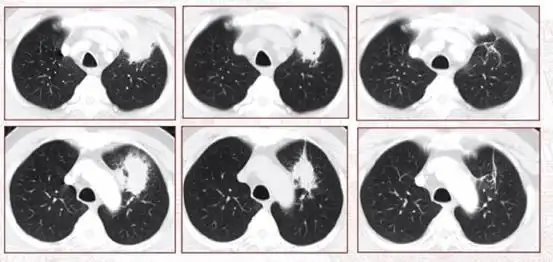

qims之窗014活动性肺结核的几种不典型ct表现及机制